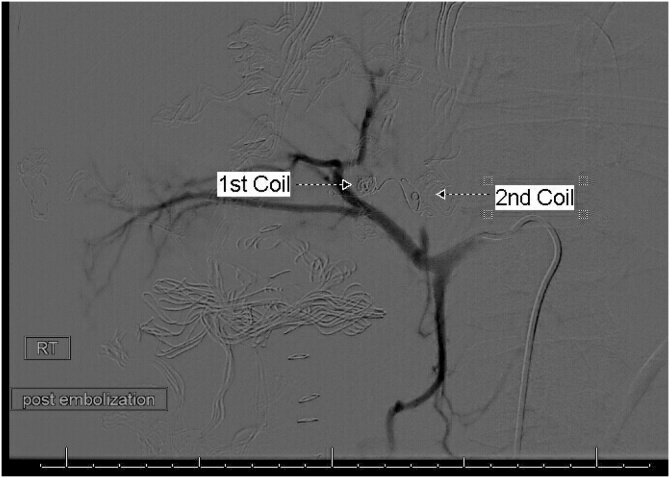

Fig. 4.

Post embolization celiac angiography shows complete exclusion of the IHPA by endo-coils.